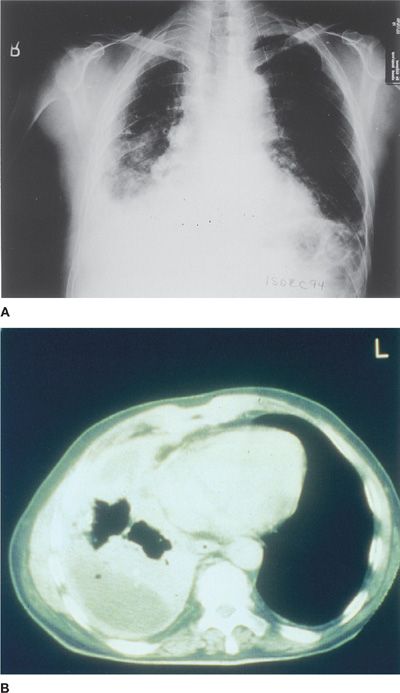

Although i'm in good health, i'm surprisingly. Investigation of a unilateral pleural effusion in adults

It is most often caused by asbestos exposure. Mesothelioma | Image | Radiopaedia.org

Learn about symptoms, treatment options and prognosis on asbestos.com. Pleural plaques from asbestos exposure â€